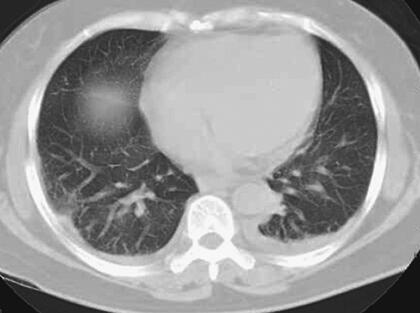

患者,女性,59岁。因“发热8天,上腹部隐痛、腹泻伴胸闷7天”于2011年7月8日入院。患者8天前出现发热,39.5℃,无畏寒、寒战,在当地卫生院予输液治疗(具体不详),症状未好转。7天前出现上腹部隐痛、腹泻,日约4~5次,黄色稀便,伴胸闷,遂就诊于当地镇医院,心电图检查正常,拟“中暑”,予针灸等治疗后无好转。2天前就诊于当地县人民医院,查血常规:WBC 8.4×109/L,N 89.2%,Hb 102g/L,PLT 92×109/L;肥达反应阴性;肝功能:ALT 104IU/L,AST 144IU/L,TP 55g/L,ALB 27g/L;腹部CT:脂肪肝,脾肿大;胸部CT:两肺少许炎症,左侧可疑少许胸腔积液,拟败血症,中毒性肝炎,伤寒住院治疗;期间体温波动于38~39℃,血压波动于80/50~90/60mmHg,予多巴胺[6.0μg/(kg·min)]升压,予亚胺培南-西司他汀钠联合头孢曲松抗感染治疗,病情无好转,仍有发热、腹泻、上腹部隐痛不适,并出现尿量减少、血肌酐升高。于7月8日转笔者医院急诊,测血压[多巴胺6.0μg/(kg·min)维持]89/55mmHg,血常规:WBC 10.28×109/L,N 89.4%;Lac 2.3mmol/L,CRP>90.0mg/L,Cr 141μmol/L,cTnI 6.02μg/L,BNP 577pg/ml;胸腹部CT:两下肺背侧散在炎症,两侧胸腔少量积液,慢肝样病变,胆囊结石(图1、图2);腹部B超:脂肪肝,脾偏大,拟发热待查,心肌炎?感染性休克?,予补液、亚胺培南-西司他汀钠控制感染,多巴胺升血压,为进一步治疗拟上述诊断收入急诊重症监护病房。既往史:40年前发现胆囊结石。

图1 胸腹部CT:两肺纹理增多增粗,两下肺背侧见斑片高密度影,边界模糊;两侧少量胸腔积液(7月8日)

关于恙虫病的肺部改变报道较多。有59%~72%的恙虫病患者可有肺部表现,胸部CT表现可以有磨玻璃影、纵隔淋巴结肿大、小叶间隔增厚、胸腔积液、肺门淋巴结肿大,间质增厚、实变,小叶中心性结节。恙虫病可伴有急性呼吸窘迫综合征(ARDS),是一种少见但很严重的并发症。年龄大、血小板减少、早期肺炎(出现呼吸窘迫前2天,胸片上出现浸润征象)均是ARDS的诱发因素。该患者表现为呼吸促,胸部CT表现为双肺纹理增多、增粗,两下肺背侧见斑片样高密度影,边界模糊;两侧少量胸腔积液,氧合指数<200,考虑并发ARDS。